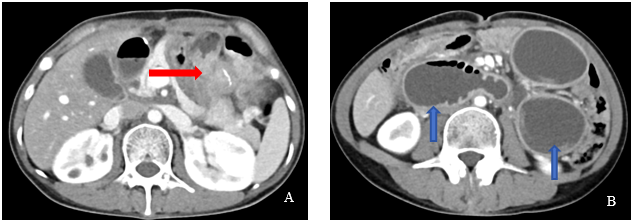

一位年轻女性胃癌患者,术后不幸复发。肿瘤像一块「巨石」,死死堵住了她消化道的关键位置——输出袢。后果很残酷:她吃下的每一口食物、喝下的每一口水,都会原封不动地吐出来,甚至混杂着黄绿色的胆汁。

不过,她的梗阻不是完全「死」的,而是留下了一道几乎无法察觉的「缝隙」。要打通它,唯一的希望是微创介入——用比头发丝还细的导丝,在这片「迷宫」中找到正确的路径。

合肥京东方医院肿瘤放疗科联合影像科韦树华主任、肿瘤科介入治疗组,像刑侦专家一样,对着患者的片子反复研判,终于在错综复杂的影像中,锁定了那条理论上可行的「生命缝隙」。真正的挑战,在手术台上。介入治疗组专家孙东旭,操控着两根导丝开始 「探险」: